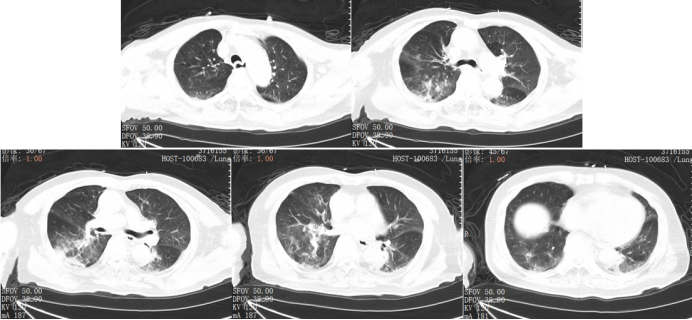

1月25日胸部CT提示双肺感染病灶较前部分吸收(图9,患者鼻导管2 L/min吸氧下,指脉氧饱和度98%,一般情况可,予以办理出院出院带药:伏立康唑片0.2 g口服(q12h利奈唑胺片0.4 g口服(q12h),定期门诊复查。

图片

9  出院前复查胸部CT(2025-01-25)

2025年2月26日患者门诊复查,未吸氧下氧饱和度正常,胸部CT双肺感染病灶基本吸收,仅残留少许纤维条索影(图10

10  出院后随访胸部CT(2025-02-26)